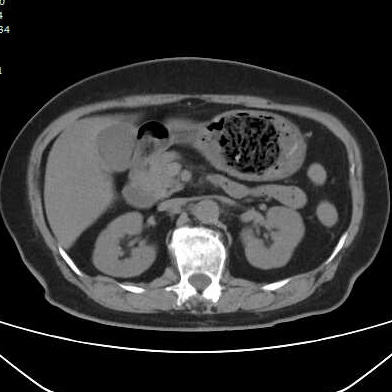

第二个病例,青年男性,也是突然腹痛,症状和第一个类似,首选腹部CT。

胃镜证实

同样治疗后痊愈出院